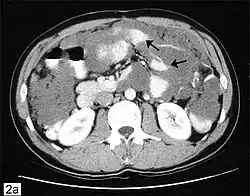

CT scanning is preferred to assess the extent of the tumor in the abdominopelvic cavity, though magnetic resonance imaging can also be used.[28] CT scanning can also be useful for finding omental caking or differentiating fluid from solid tumor in the abdomen, especially in low malignant potential tumors. However, it may not detect smaller tumors. Sometimes, a chest x-ray is used to detect metastases in the chest or pleural effusion. Another test for metastatic disease, though it is infrequently used, is a barium enema, which can show if the rectosigmoid colon is involved in the disease. Positron emission tomography, bone scans, and paracentesis are of limited use; in fact, paracentesis can cause metastases to form at the needle insertion site and may not provide useful results.[29] However, paracentesis can be used in cases where there is no pelvic mass and ascites is still present.[29] A physician suspecting ovarian cancer may also perform mammography or an endometrial biopsy (in the case of abnormal bleeding) to assess the possibility of breast malignancies and endometrial malignancy, respectively. Vaginal ultrasonography is often the first-line imaging study performed when an adnexal mass is found. Several characteristics of an adnexal mass indicate ovarian malignancy; they usually are solid, irregular, multilocular, and/or large; and they typically have papillary features, central vessels, and/or irregular internal septations.[31] However, SCST has no definitive characteristics on radiographic study.[32]

Secondary ovarian cancer

Ovarian cancer can also be a secondary cancer, the result of metastasis from a primary cancer elsewhere in the body.[26] About 5–30% of ovarian cancers are due to metastases, while the rest are primary cancers.[80] Common primary cancers are breast cancer, colon cancer, appendiceal cancer, and stomach cancer (primary gastric cancers that metastasize to the ovary are called Krukenberg tumors).[26] Krukenberg tumors have signet ring cells and mucinous cells.[29] Endometrial cancer and lymphomas can also metastasize to the ovary.[81]